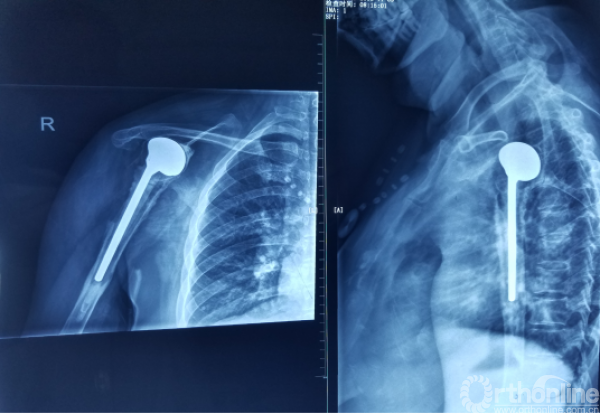

术后X线

1.抗生素骨水泥占位器植入

2.不锈钢克氏针+抗生素骨水泥

3.柄部没有骨水泥,利于引流,头部较原有假体头部偏大,减少挛缩,占位关节腔,颈干角及后倾维持

12.骨水泥头较原有假体略大,充分占位

13.要尽量保证骨水泥界面的光滑和平整

14.对于少量的骨水泥残存在不影响大局情况下可以减少不必要的骨质破坏